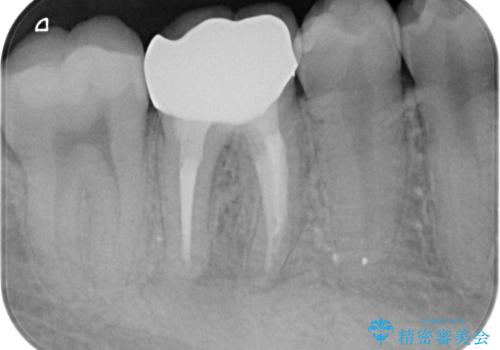

- 右下の奥歯がうずくとのことで来院されました。

根管治療を行った後、セラミックのかぶせ物を装着します。

- 右下6 精密根管治療(大臼歯・リトリートメント):143,000円 土台:22,000円 仮歯:11,000円 ジルコニアクラウン:121,000円 合計297,000円費用は治療当時の料金となります

治療後は症状も改善し、半年後の経過も良好です。